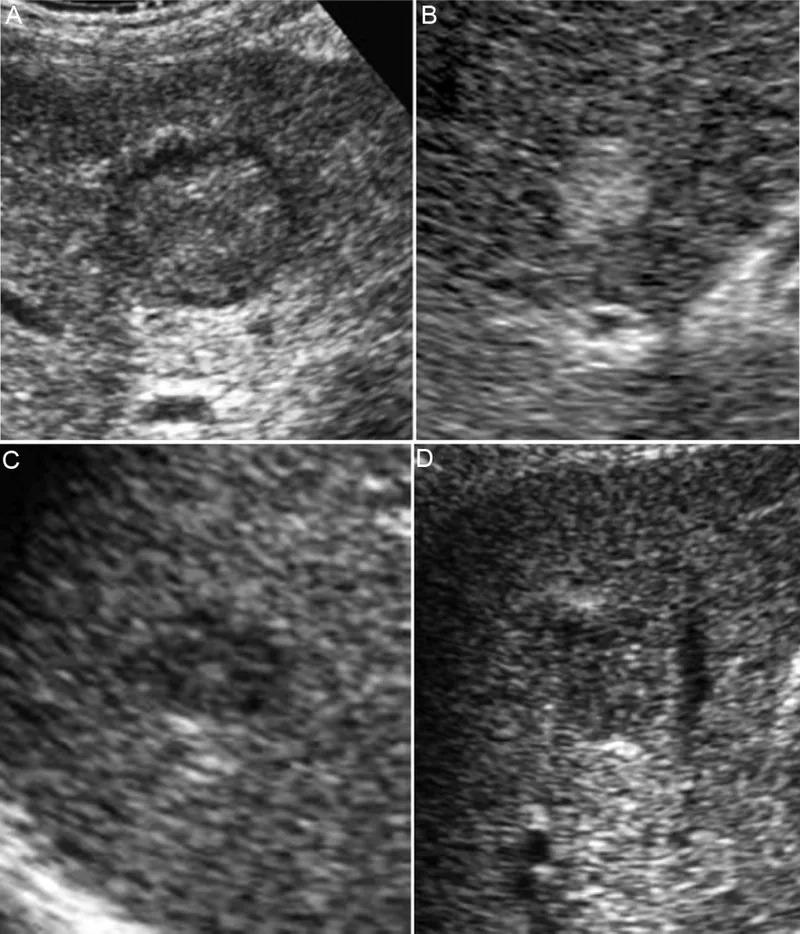

- For all cirrhotic patients: abdominal ultrasound ± AFP every 6 months.

- HCC Surveillance: For patients with cirrhosis, ultrasound (US) with or without alpha-fetoprotein (AFP) every 6 months.

- Regular ultrasound screening for HCC is crucial for patients with HCV-induced cirrhosis.